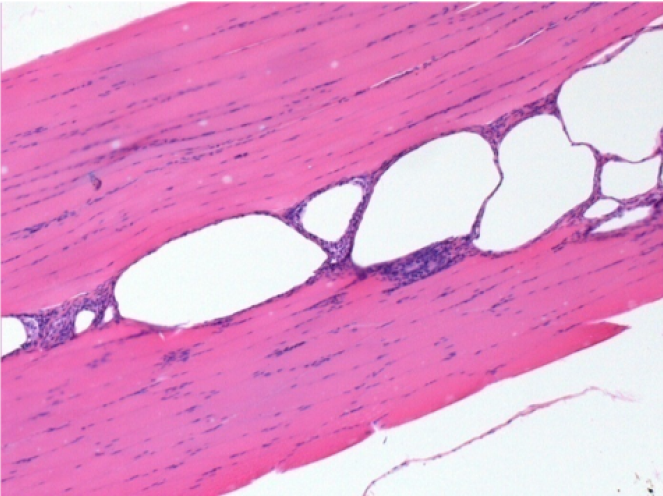

7 meses (D210) después de la inyección IM de Endopeel 0,1 ml en el músculo pretibial derecho.

Restitutio ad integrum (restauración a la condición original) completa después de 7 meses

L :Control 50xD210

R50X-D210